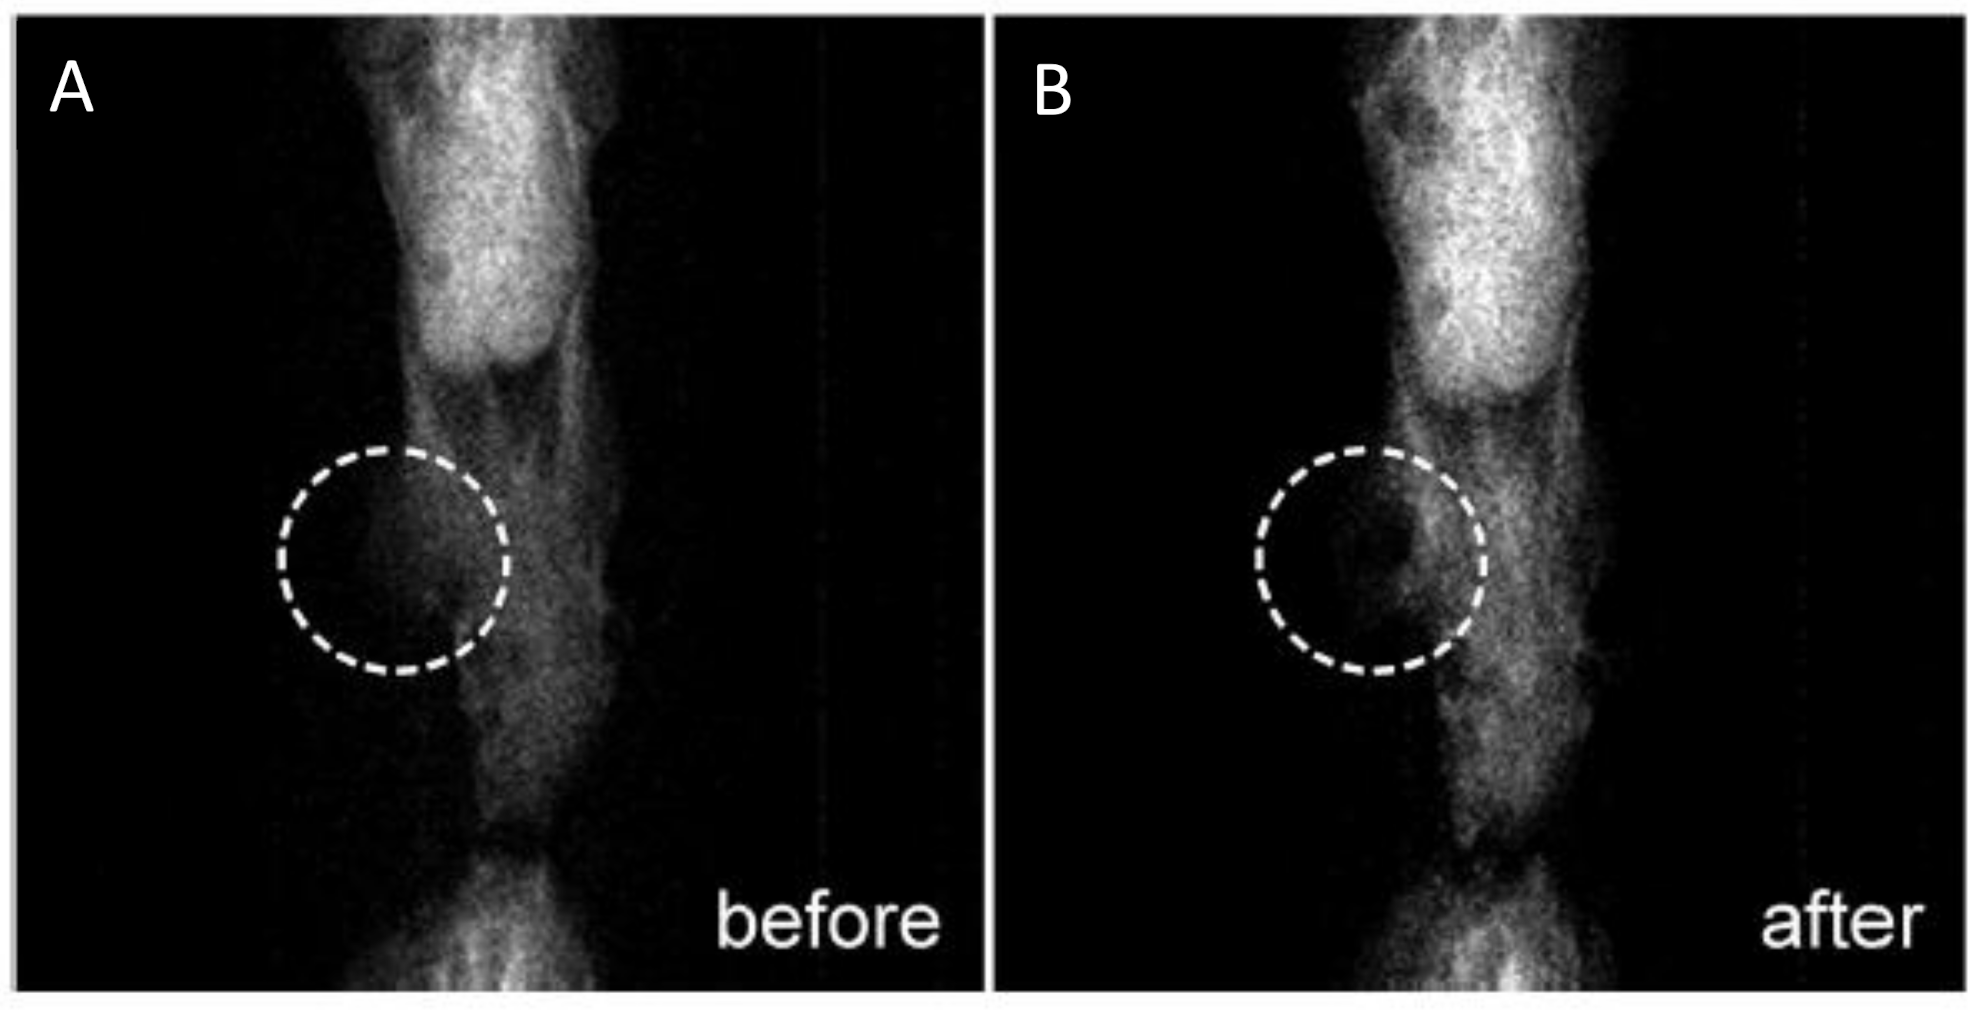

- Mehrmohammadi, M.; Shin, T.-H.; Qu, M.; Kruizinga, P.; Truby, R.L.; Lee, J.-H.; Cheon, J.; Emelianov, S.Y. In vivo pulsed magneto-motive ultrasound imaging using high-performance magnetoactive contrast nanoagents. Nanoscale 2013, 5, 11179–11186. [Google Scholar] [CrossRef] [Green Version]